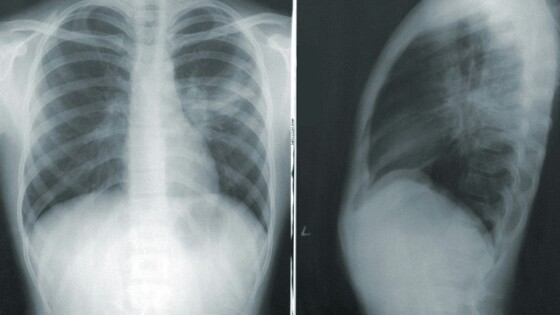

Но ведь опухоль на первой и второй стадии может достигать размеров от 3 до 6 см. Это достаточно большие опухоли, неужели их не видно на рентгене или флюорографии на этих стадиях?

— Их видно. Проблема заключается в том, что размер опухоли — это только часть проблемы. Вторая и третья части — это распространение опухоли и ее гистологическая структура, наличие метастазов. Размер опухоли напрямую коррелирует с распространенностью. То есть чем больше размер опухоли, тем чаще мы встречаемся с наличием отдаленных метастазов.

Поэтому общее правило для всех онкологических заболеваний — не дожидаться, когда опухоль достигнет больших размеров, а выявлять эту опухоль на предельно ранних стадиях. И вот с этим в рентгенографии очень большая проблема: найти маленький, сантиметровый или даже иногда двухсантиметровый одиночный очаг в легочной ткани очень сложно. И даже самые современные аппараты часто не позволяют точно и своевременно это сделать. Это не значит, что найти маленький очаг на рентгенограмме невозможно, но это скорее исключение, чем правило.

Это подтверждают исследования ученых РМАНПО, НМИЦ онкологии им. Блохина, Российского биотехнологического университета и компании «АльфаСтрахование-ОМС». Согласно данным исследования, рентгенография и флюорография органов грудной клетки совсем не «видят» рак легкого на первой стадии, пропускают большинство случаев рака легкого на второй стадии и половину случаев на третьей. С помощью обычной рентгенографии не удалось достоверно определить признаки рака легкого на ранних стадиях в 84,3% случаев. Вероятно, из-за неэффективности такой диагностики одногодичная летальность с момента установления диагноза «рак легкого» в два раза превышает данный показатель у онкологических пациентов.

— Нет, рак легкого можно и необходимо выявлять при рентгенографии. Сегодня именно так и происходит в обычной практике. Но мы говорим о суперранней диагностике, когда размеры очага в легком не превышают 1–2 см. Именно такие одиночные очаги труднее всего заметить на рентгеновском снимке. Для более крупных образований рентгенография — вполне надежный метод диагностики. Нельзя забывать, что во второй половине прошлого века она сыграла колоссальную роль в ранней (по тем представлениям) диагностике заболеваний органов дыхания, будь то рак легкого или туберкулез. Вся система раннего выявления этих заболевания в позднем СССР была основана именно на проверочной флюорографии.

При этом сегодня есть способ, который может существенно улучшить диагностику рака легкого на гораздо более ранней стадии — это низкодозная компьютерная томография (НДКТ). Ее внедрение в профилактические мероприятия позволит увеличить выявляемость рака легкого на ранних стадиях в два-три раза.